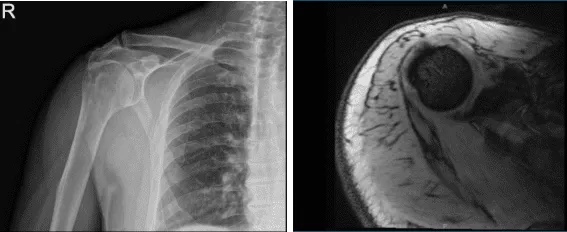

Me hicieron radiografías del hombro derecho. El hombro derecho mostró tendinitis calcifica. Estrechamiento de la articulación glenohumeral así como del espacio acromiohumeral. Cambios degenerativos de la articulación acromioclavicular. Se recomienda una resonancia magnética del hombro derecho.

Los resultados de la resonancia mostraron una causa significativa de dolor: tendinitis calcifica por Infraspinatus. Tendinosis del manguito rotador y una rotura de la superficie bursal de espesor parcial moderado del tendón supraespinoso con tejido de atenuación mezclado.

Desgarro superficial articular de espesor parcial leve del tendón subescapular. También se detectaron artrosis moderada de la articulación AC y desgarro focal del labrum superior en la unión condrolabral.

Resonancia magnética Radiografía del hombro derecho